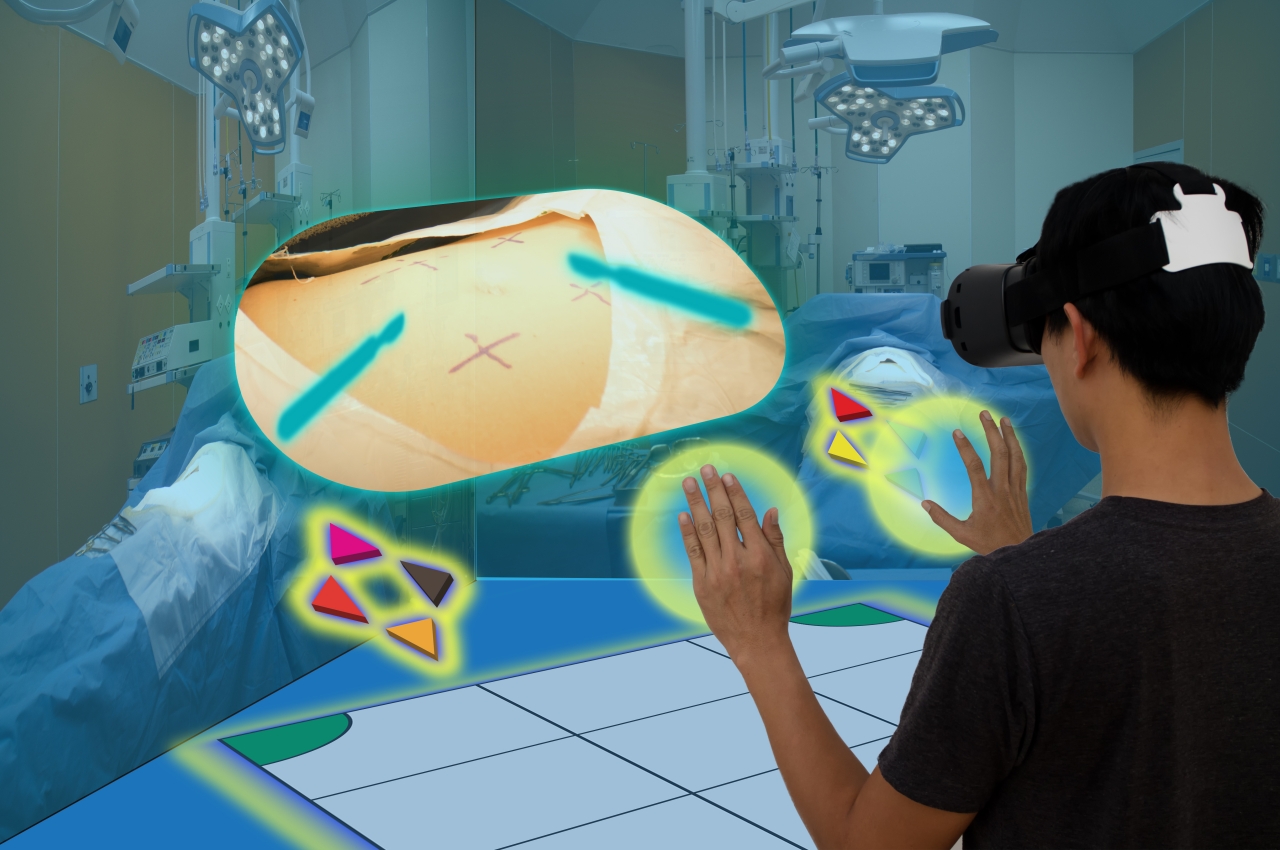

Formazione e consultazione in telepresenza

Questo tipo di comunicazione visiva può essere fondamentale non solo per mantenere le persone socialmente vicine mentre fisicamente separate, ma anche per far girare il mondo anche quando sono chiusi in casa. La recente pandemia di COVID-19 ha costretto molte persone a ricorrere alle videochiamate per il lavoro e anche per gli appuntamenti dal medico. La telemedicina è diventata una cosa negli ultimi due anni, ma le cose non si fermeranno qui. Con l'aiuto delle applicazioni VR e AR, il personale medico e gli operatori sanitari possono estendere la loro portata, anche quando la realtà non è di fronte a loro.

No, questo non è lo scenario spaventoso di eseguire interventi chirurgici a distanza (ci arriveremo più avanti) ma il semplice caso di formare il personale o addirittura informare i pazienti attraverso canali virtuali. Anche se niente batte davvero la realtà, ci sono alcune informazioni, come imparare a usare i macchinari, che non hanno davvero bisogno di formazione di persona per la maggior parte del tempo. E se diagrammi e grafici sono efficaci nell'educare i pazienti su varie malattie e condizioni mediche, immagina come una dimostrazione più interattiva e realistica nel Metaverso possa essere più efficace.